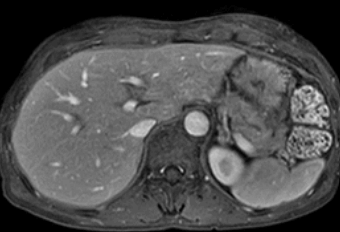

얼굴의 색이 어둡게 변하고 눈이 노랗게 변하면 간암을 의심해야합니다.